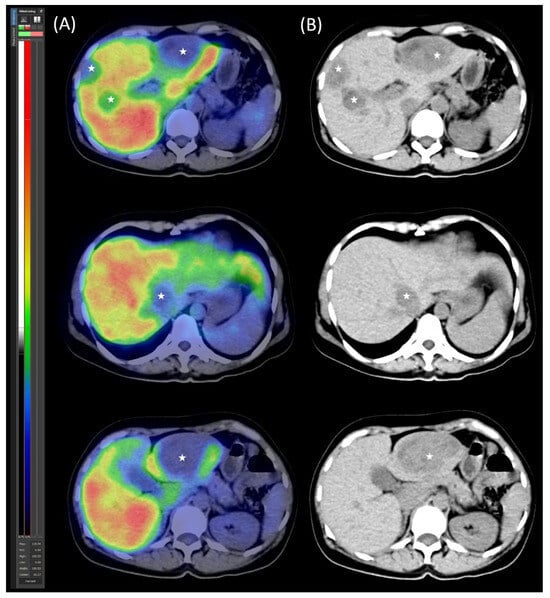

On 30 November 2020, [99mTc]Tc-EDDA/HYNIC-TOC somatostatin receptor scintigraphy with SPECT/CT was performed using a native, low-dose protocol. Oral contrast (1000 mL of polyethylene glycol solution) was administered 60 min prior to imaging to promote bowel distention without introducing contrast material-induced attenuation correction artefacts. The imaging revealed increased radiopharmaceutical uptake in CT-identified lesions, consistent with somatostatin receptor expression (Figure 1). Serum chromogranin A (CgA) levels were moderately elevated at 108 ng/mL (reference range: 19.0–98.0).

Figure 2. [99mTc]Tc-mebrofenin SPECT/CT. (A) Transaxial SPECT/CT and (B) native low-dose CT images illustrate the distribution of functional hepatocytes and metastases. The metastases appear as hypodense, photopenic areas (marked with stars).